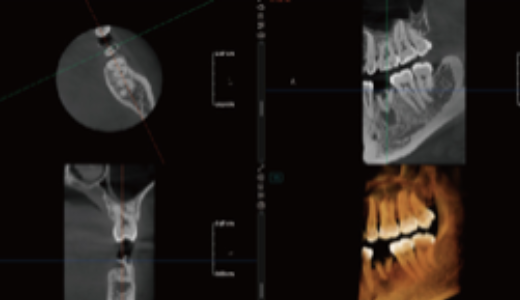

Visualização 3D do Seio Maxilar

Gera automaticamente a estrutura 3D do seio maxilar.

Permite uma observação clara da morfologia do seio e ajuda a avaliar os riscos cirúrgicos em implantes maxilares.

Auxilia na avaliação do volume de enxerto em elevação do seio maxilar

Planeamento Virtual de Implantes

Permite a simulação de procedimentos de implantes (implante + pilar + coroa), ajudando a selecionar o implante mais adequado.

Fornece alertas de proximidade ao canal nervoso, aumentando a segurança cirúrgica.

Facilita a comunicação entre médico e paciente, permitindo ao paciente visualizar claramente o procedimento de implante planeado.